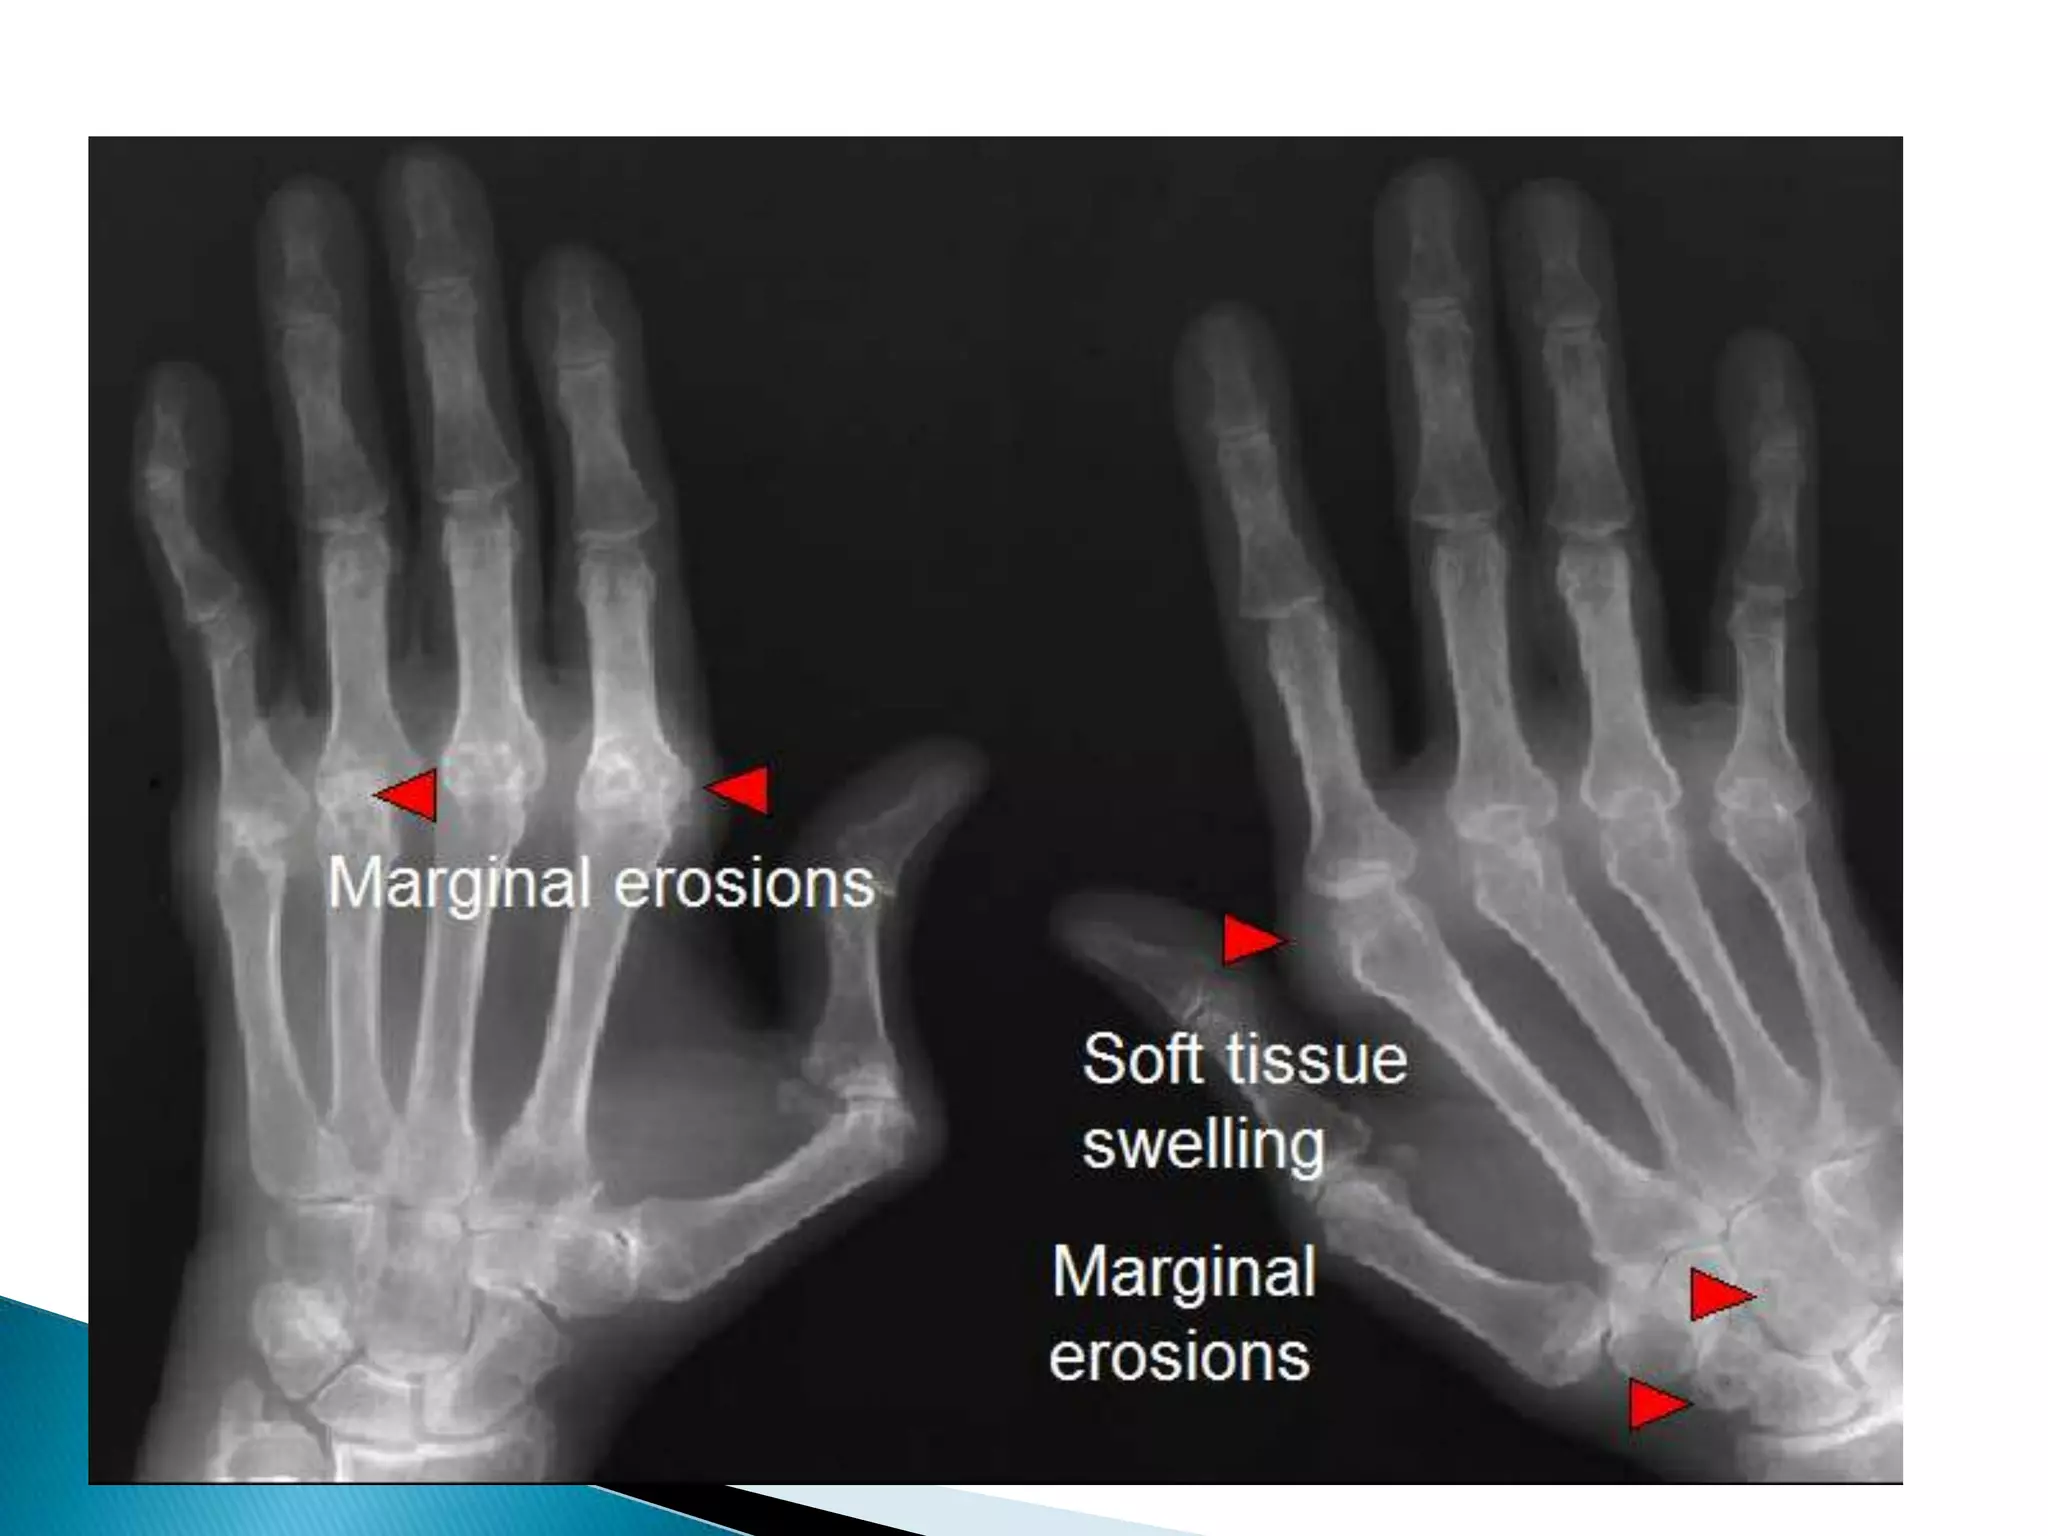

2-Soft tissue swelling;Periarticular soft tissue swelling is  a feature of inflammatory  & infective arthritis.Discrete asymmetrical periarticular soft tissue swelling can be seen in gout due to gouty tophi

Radiological features of RA

1-Joint space narrowing;It occur in all forms of joint diseases except avascular necrosis.

2-Soft tissue swelling;Periarticularsoft tissue swelling is a feature of inflammatory & infective arthritis.Discrete asymmetrical periarticular soft tissue swelling can be seen in gout due to gouty tophi

No periarticular soft tissue swellingRAJoint space narrowing uniform.